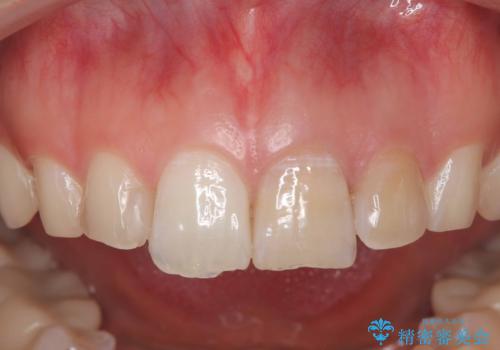

「数日前から前歯に痛みがある」「左上1、2番の色が気になる」

診査・診断:

左上1番および2番は失活歯であり、両歯ともに失活に伴う変色を認めました。左上2番に関しては根尖部に透過像を認め、根尖性歯周炎と診断しました。これが前歯部の痛みの原因と考えられました。